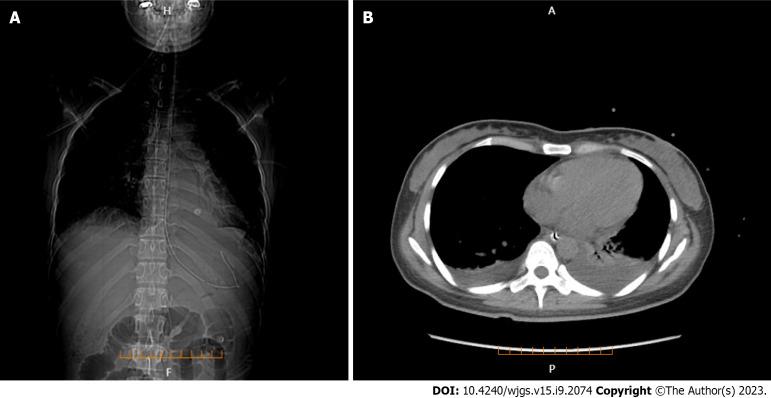

A previously healthy 27-year-old woman presented with abdominal pain following a history of fatigue and consumption of cold water. Laboratory investigations, physical examinations, and enhanced abdominal computed tomography (CT) suggested systemic lupus erythematosus complicated by LMV. She received treatments, such as GI decompression, somatostatin, glucocorticoids, and immunosuppressants, and was evaluated using color ultrasonography. Twenty days later, the patient reported no stomach discomfort and was able to consume semi-liquid food. Laboratory investigations showed that inflammatory factors decreased to normal levels and complement levels increased slightly. One year after discharged, she recovered with methylprednisolone being tapered to 4 mg per day, mycophenolate mofetil to 0.75 g bid, and hydroxychloroquine to 0.2 g bid; however, only C3 complement level was slightly below the normal level.

Early diagnosis of LMV is essential for successful treatment; this depends on a combination of clinical manifestations, laboratory investigations, and imaging findings. Enhanced CT is preferred, but ultrasonography can be used for prompt screening and follow-up.